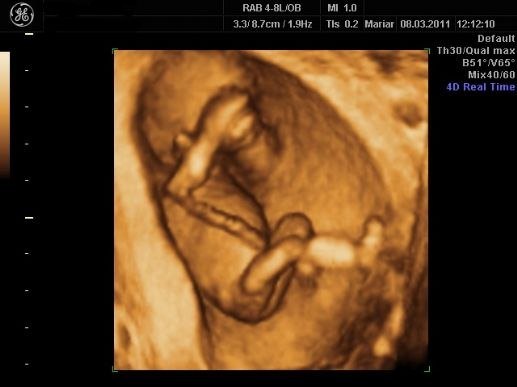

Desværre lå moderkagen foran så billederne blev ikke ret gode men her er et par stykker:

Min moderkage ligger nemlig også foran, men syntes stadig at billederne er helt fine